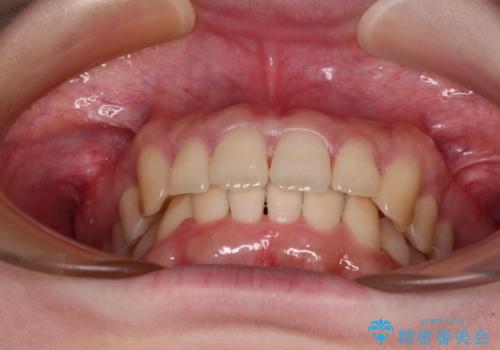

- 全体的な歯列の叢生を気にして来院された患者様です。

奥歯の咬み合わせを見ると、片方は上顎が下顎に対して相対的に前方にあり、他方は交叉した咬合の状態でした。

咬み合わせを改善するためには、上顎臼歯を後方に移動させた咬み合わせにする必要があります。

インビザライン単体で改善することも可能ですが、ディープバイトのためインビザライン単体で達成する可能性が低いと考えられたため、カリエール・ディスタライザーという補助装置を併用して、より確実性を上げることとしました。

カリエール・ディスタライザーを使用している期間、反対側はワイヤー矯正により叢生を解消していくこととしました。

奥歯の咬み合わせを改善しながら、並行してインビザラインで歯列を整えることとしました。